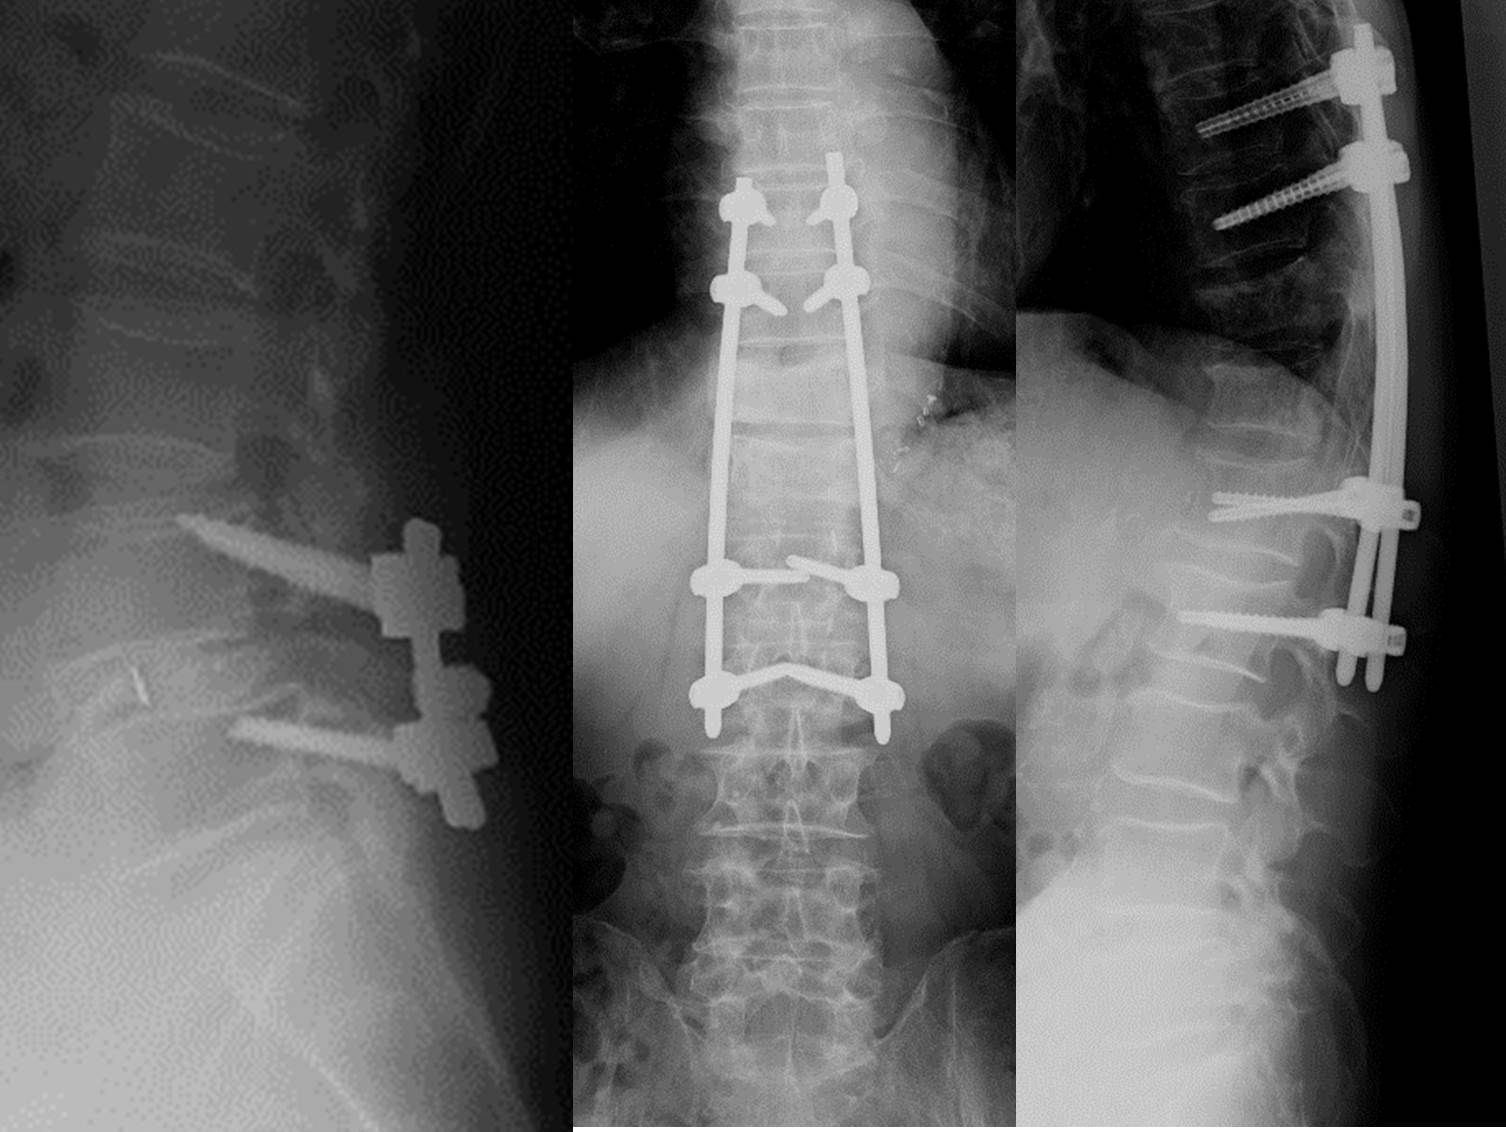

固定術

背骨は身体を支えるという機能の他に身体の運動に関与するという機能も持ち合わせています。隣接した背骨の運動範囲(可動域)が必要以上に大きくなることで強い痛みが生じたり、神経が圧迫されてしびれ、感覚障害などが出現する事があります。可動域が一旦大きくなると回復する可能性は少なくなり、通常の減圧術だけでは治療が中途半端に終わってしまう場合には、その部分を固定する必要が出てきます。チタン性のスクリュー(ボルト)、ロッド(インプラントと総称します)などにて隣接する脊椎骨を固定します。その部分の可動性を無くしてしまう必要がある場合があります。使用する金属材料は非常に優れたもので、将来的に破損する可能性は極めて低いものですが、絶対的な信頼性があるとも言えないので、インプラントによる固定だけではなく、周囲に患者さまの自身の骨組織を移植することで将来的に完全な固定状態を得る必要があります。移植する骨組織は一般的には削除した骨組織でまかなわれる場合と、骨盤などから移植用の骨組織を別途に採取する必要がある場合があります。